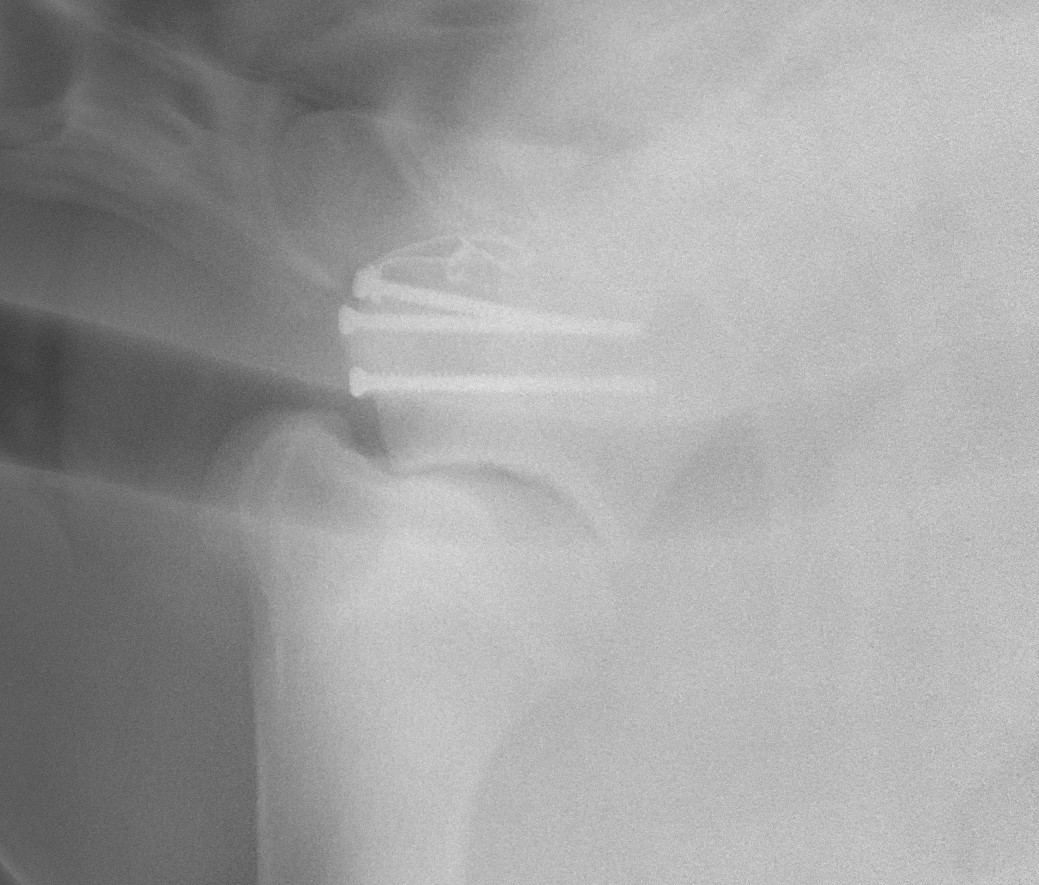

A pre-surgical consultation is important so you fully understand the reason your horse requires surgery and to establish what steps are necessary prior to and after the procedure. During this consultation, results of lameness examination and diagnostic imaging are discussed so it is important to provide these to the surgeon ahead of time if they were performed by your regular vet. Sometimes one or more of these studies will need to be repeated, if sufficient time has elapsed between the original study and the surgery date.